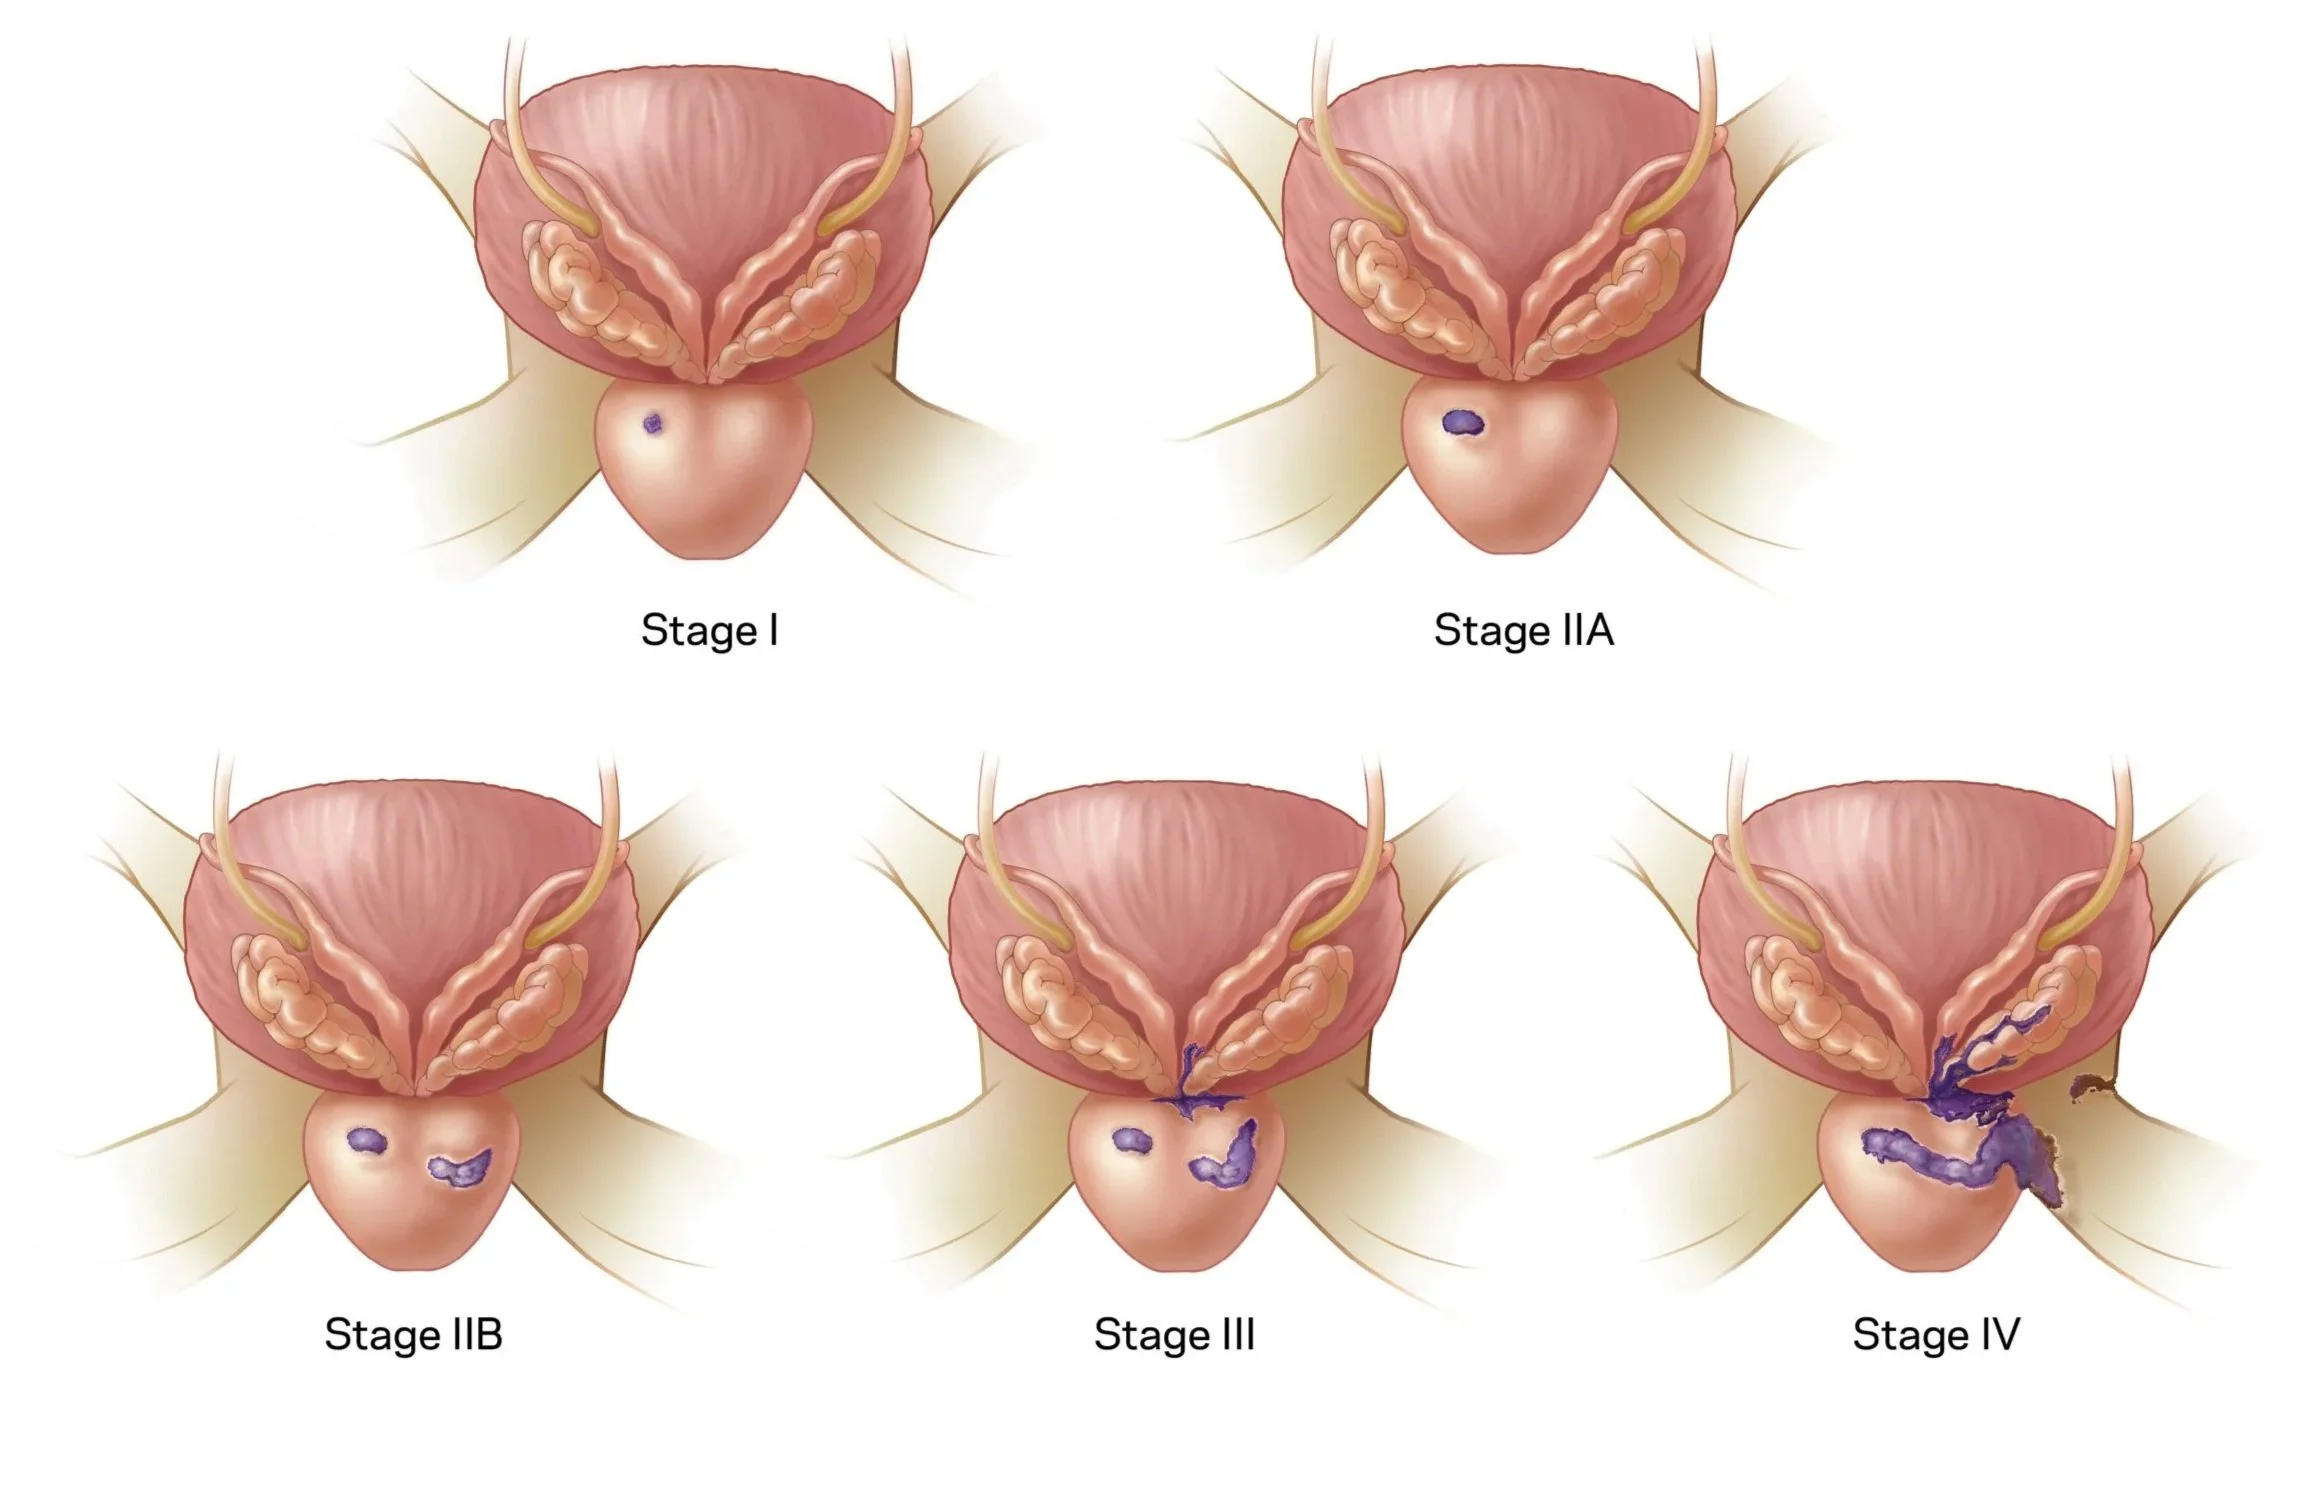

Surgical illustrations visually depict operative techniques, surgical anatomy, and complex procedures. They are created with high anatomical accuracy and serve as a visual bridge between complex surgical knowledge and learners, clinicians, or patients.

Prostate Cancer Booklet

Created clear, accurate, and visually engaging medical illustrations for a patient education booklet on prostate cancer for a hospital system. The illustrations simplified complex anatomical and clinical concepts, helping patients better understand diagnosis, treatment options, and disease progression.

Client: Northwell Hospital System

Patient Education: Prostate Cancer